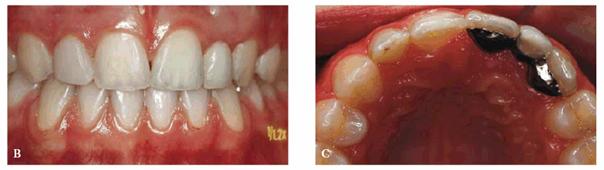

Approach

A male patient, 36 months old.

PROBLEM: He presented with rampant caries involving four maxillary

anterior teeth and caries in the lower arch. The parents hoped that the teeth

could be saved. Initial radiographs were taken (Figures 27-2A

and B

Figure 27-2A and B: Rampant caries involving the anterior teeth and the lower arch.

TREATMENT: Caries were removed, and endodontic treatment was performed.

Aluminum oxide posts were used. A rubber-base impression was made for

laboratory-processed full acrylic crowns (Figure 27-2C

Figure 27-2C: Crowns are seated with an acceptable result.

RESULT: Crowns were seated with an acceptable result. Figures 27-2A and 27-2D show the sharp contrast between

before and after treatment. The child was able to resume his usual activities

without discomfort or fear of future embarrassment.

Figure 27-2D: The radiograph shows the endodontic treatment performed and the restoration of the lower caries.